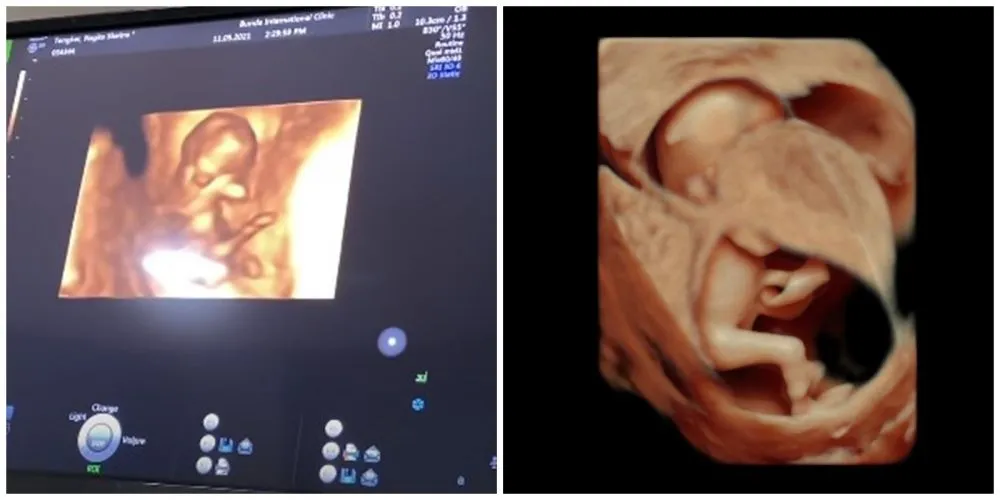

Dalam channel YouTube Rans Entertainment, Nagita Slavina membagikan momen saat dirinya melakukan cek USG 4D. Dengan teknologi tersebut, Gigi bisa melihat perkembangan janinnya lebih jelas.

Calon adik Rafathar itu terlihat aktif dalam pemeriksaan dokter. Sempat khawatir dengan keadaan calon anak keduanya, Gigi pun sekaligus berkonsultasi dengan dokter yang menangani.

8. Yang nggak kalah menarik, sang bayi pun justru tampak memiliki pergerakan yang aktif. Pemandangan ini membuat Gigi ikut bahagia.

10. Apalagi dengan potret sang bayi yang terlihat semakin jelas dalam pemeriksaan itu. Dokter pun menambahkan bahwa sang janin juga dalam kondisi normal. Banyak penggemar yang ikut merasa gemas nih dengan calon anak kedua Raffi dan Nagita.